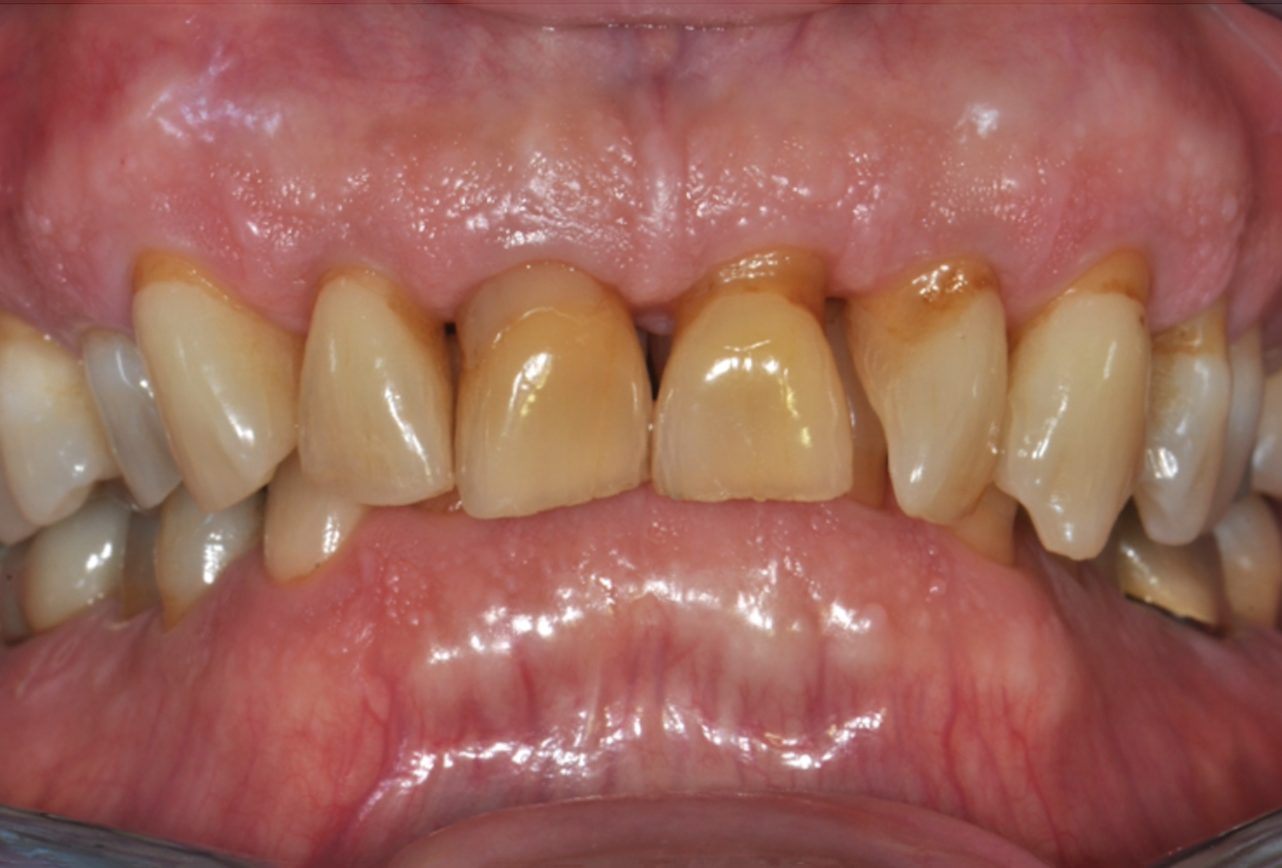

Fig 3. Pretreatment views: right lateral (Fig 2), frontal (Fig 3), and left lateral (Fig 4). Note: The maxillary right first molar (tooth No. 3) (Fig 2) would be identified as the most periodontally involved molar that was planned to be maintained.

Figure 3

Periodontal examination revealed generalized BOP and PDs up to 9 mm in the maxillary and mandibular molars with multiple furcations in each molar (Figure 2 through Figure 7). He presented with class I mobility in many posterior teeth and class II mobility in teeth Nos. 3 and 9 (maxillary right first molar and maxillary left central incisor, respectively). The periodontist decided to score tooth No. 3 for the PRS, as this was the most periodontally involved molar that was planned to be treated and maintained (Figure 2 and Figure 8). This tooth (maxillary right first molar = score 1) presented with probing depths of 7 mm (score 1); three total furcation invasions (score 3) (mesial [degree II furcation], buccal [degree I furcation], and distal [degree II furcation]); and a class II mobility (score 2). The total PRS for tooth No. 3 was 8, representing a "guarded" prognosis. Based on this score, the likelihood of not losing any teeth to periodontal disease for 15 years was 81%, and for 30 years the likelihood was just 56% (Figure 9).7